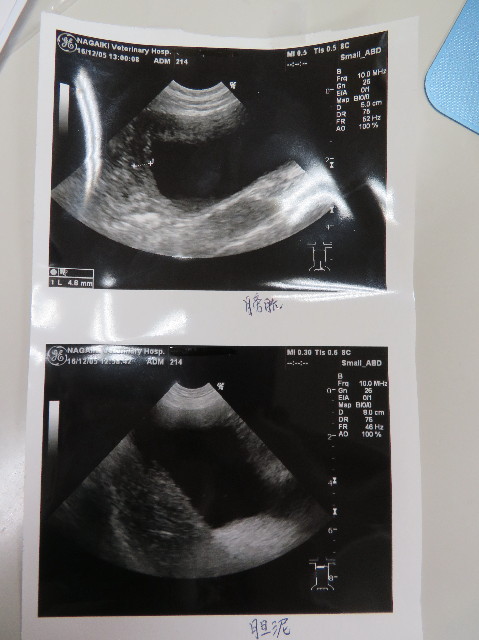

●エコー

○膀胱少し腫れているが大丈夫

○胆泥、たまっている(かわりなし)

○胆嚢、大丈夫